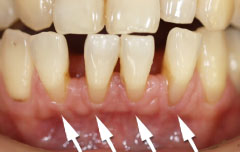

| 歯周病が進行したケースでは盲目下でポケット内の歯石を確実に除去するには限界があります。 | 局所麻酔をした後、歯茎を切開し、明視下にて歯根面の歯石や炎症組織を取り除き、歯周ポケットの除去をおこないました。 |

| 一見分りませんが、かなり歯周病が進行していました。歯周ポケットの改善や歯槽骨を平坦にして清掃しやすい環境を整えます。数ヶ月、歯肉の盛り上がりを待ってから適合の良いクラウンを被せます。 | ||